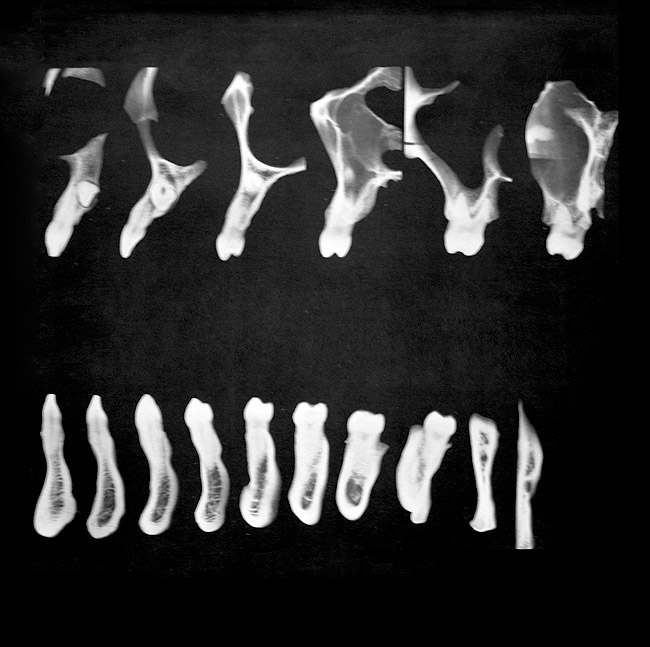

Figure 6  Tomograms showing natural teeth alignments on their bony bases (from Wheeler’s Dental Anatomy, Physiology, and Occlusion Textbook).

Figure 6

Figure 7  Implants placed more in alignment with natural tooth roots.

Figure 7

Another concern for loading of dental implants is implant alignment. When placing implants for the edentulous patient and an overlay or hybrid restoration is planned, the implants should then be placed as parallel as possible and slightly lingual to the actual tooth position. This allows establishment of normal contours of the prostheses and space for placement of the prosthetic teeth. Implants should not be placed in the central incisor region for a maxillary overlay prosthesis because this will compromise palatal contours, thereby affecting speech and tongue function. If, however, implants are planned for the partially edentulous patient and the replacement is for a natural tooth or teeth, then implants should be placed more in line with the long axis of the natural root. Teeth are designed to better handle the multitude of directional loads encountered during mastication when properly aligned on their bony base. Implants placed more in line with natural tooth roots that are properly positioned on their bony base may allow implants to better endure the various functional loads while promoting the continual physiologic bone remodeling necessary for long-term implant survival (Figure 6 and Figure 7 ). Depending on the type of anticipated function and the presence or signs of parafunctional habits, use of a maxillary biteplane/nightguard may be indicated (Figure 8). This can reduce the possibility of lateral loads, which have a detrimental effect on the dental implant(s). The biteplane is adjusted in centric relation with simultaneous occlusal contacts and shallow anterior guidance.